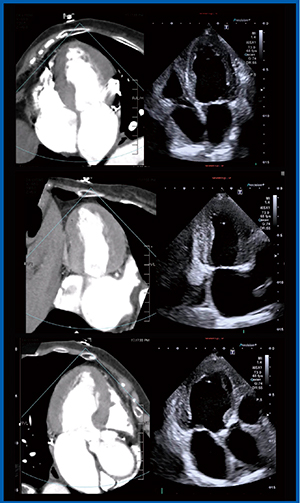

実際に,心尖部を適切に描出できた画像(図3 a)とできなかった画像(図3 b)を比較してみると,適切な画像では弁輪部からの距離が7cm,適切でない画像では6cmと,10%以上のズレがあった。こうしたズレは,左室容積やEFの計測結果の大きな誤差につながるため,2つの画像の違いをしっかりと確認できることは大変有用である。

図3 心尖部像の描出におけるFusion Imagingの

教育的効果

また,4chamberから2chamber,3chamberへと回してスキャンすることは,若手の技師はもとより,われわれにとっても難しいことである。しかし,Fusion Imaging(図4)を用いることで,2chamberではしっかり右室が消えるところを描出する,あるいは左心耳が見える断面であるといったことをCT画像と同期して見せられる点も,非常に有用と考えている。

図4 心尖部像の描出におけるFusion Imagingの

上段:四腔像,中段:二腔像,下段:三腔像